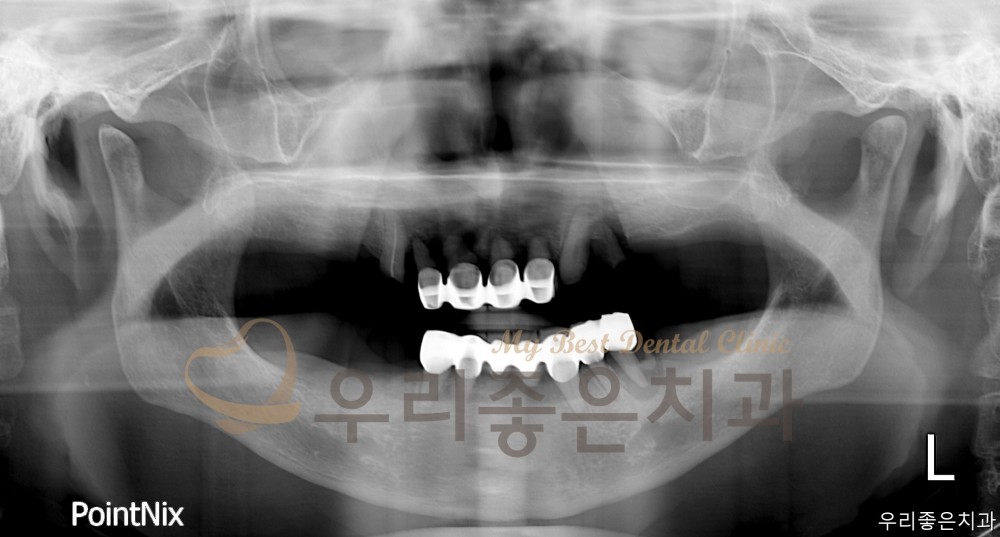

인쇄 목록 임플란트 | 우리좋은치과 상악 임플란트 풀케이스 (김** 25.03.25~25.08.13) 페이지 정보 우리좋은치과 549 0 2025-09-30 16:10:45 본문 BEFORE AFTER Before After Before After 우리좋은치과 상악 임플란트 풀케이스 인쇄 목록 이전글 ▲우리좋은치과 앞니 충치로 인한 레진 치료 (신** 25.10.02 당일치료) 다음글 ▼우리좋은치과 앞니 재보철 치료 (유 ** 25.09.23~25.09.30) 댓글목록 등록된 댓글이 없습니다. 이전글 다음글 목록